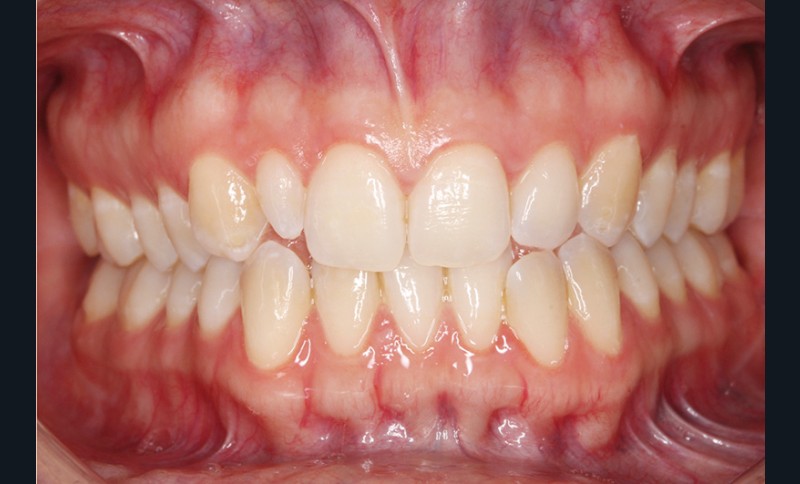

Elle présente une classe I dentaire en denture adulte. Son sourire est perturbé, notamment par la microdontie de son incisive latérale maxillaire droite (la 12). On constate un encombrement modéré au maxillaire (bimarginotopie mésio-palatine et disto-vestibulaire de 13) et plus marqué à la mandibule (monomarginotopie mésio-vestibulaire de 32 et de 43) (fig. 1-6).

Les milieux inter-incisifs ne sont pas coordonnés, à torts partagés, avec une légère déviation à droite du milieu inter-incisif maxillaire et une déviation plus marquée à gauche du milieu inter-incisif mandibulaire ainsi que du point menton. 32 et 33 présentent une tendance à l’exoclusion.